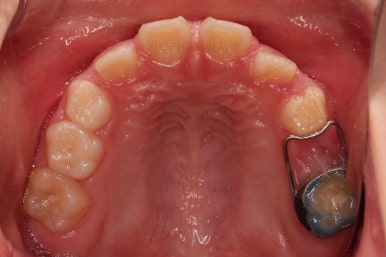

장치 사용 4달째 모습입니다.

벌써 개방교합이 개선되고 있고, 반대교합도 많이 좋아져서 거의 위아래 앞니가 비슷한 위치까지 왔네요.

왼쪽 하단 사진의 어금니에 있는 금속성 장치는 band & loop(밴드 앤 루프)라고 하는 공간유지장치인데요. 오래 써야하는 유치가 일찍 빠지는 바람에 그 공간을 잡아두는 장치입니다.